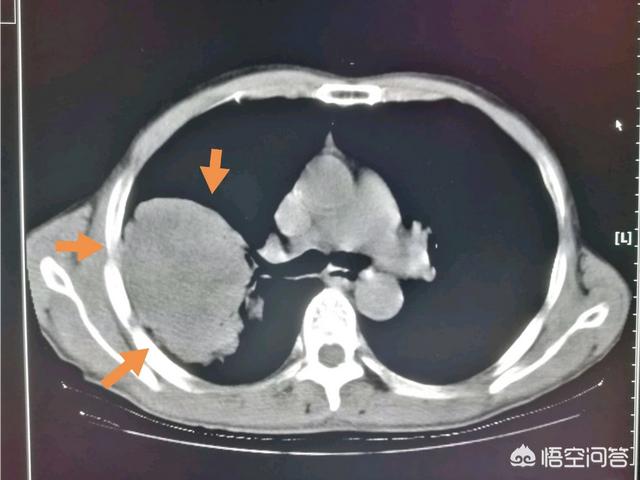

上图就是一位比较早期的食管癌病人。手术成功切除食管中下段。把食管上段和胃吻合。已经八年半了。恢复得很好。

这是一位73岁的大细胞癌。肿瘤9厘米。手术做了好几个小时。成功切除!